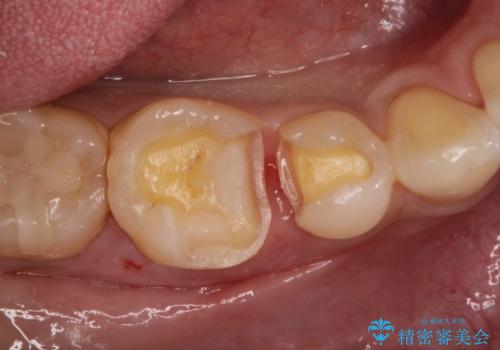

- メタルインレーによる審美障害を主訴に来院されました。

セラミックインレーに治療を行っております。

e-max プレスインレーにて修復治療を行っているため適合性及び審美性の高い治療を行うことができます。